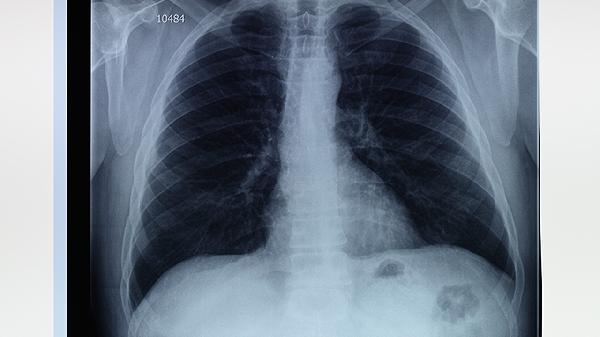

病理学检查显示,肺气肿患者的肺泡间隔断裂融合,肺大泡壁由变薄的肺泡上皮构成,未见病毒包涵体或结核结节等传染性病变特征。影像学上表现为透亮度增高的无灌注区,与感染性病变的浸润影截然不同。